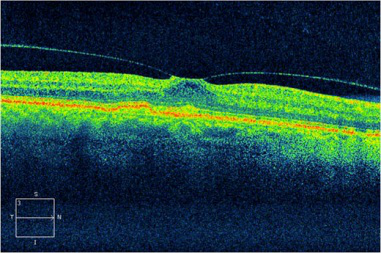

(OCT檢查顯示眼睛的黃斑前膜,纖維膜在黃斑表面產(chǎn)生牽拉的力量,可引致黃斑水腫或裂孔,引致視野中央出現(xiàn)暗點(diǎn))